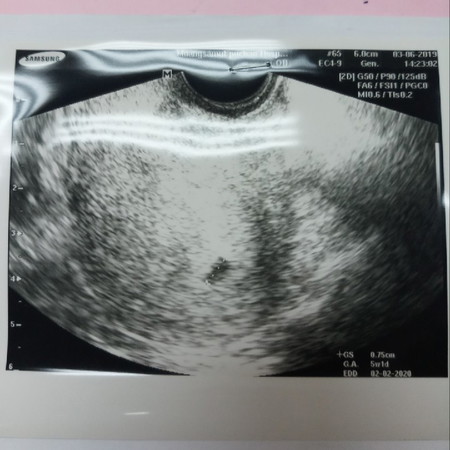

พอดีเราไปซาวด์มา เพราะมีเลือดสีน้ำตาลติดกางเกงใน เลยกังวลใจ หมอซาวด์ทางช่องคลอดถุงยังเล็กมาก ยังไม่เจอน้องเลย หมอบอกครรภ์ยังอ่อนหรือไม่น้องอาจฝ่อไปแล้ว ? ตอน 5 วีคมีใครเป็นเหมือนเราไหมคะ กลัวจัง หมอนัดซาวด์อีกที 2 อาทิตย์

ตอน5วีคค่ะ ซาวผ่านช่องคลอดถึงเจอค่ะ แต่เจอแต่ถุงการตั้งครรภ์ ตอนนี้14วีคแล้วค่ะ

ของบ้านนี้ซาวด์เจอแต่ถุงจ้า คุณหมอบอกท้องอ่อนอยู่ให้รอซาวด์รอบหน้า😂